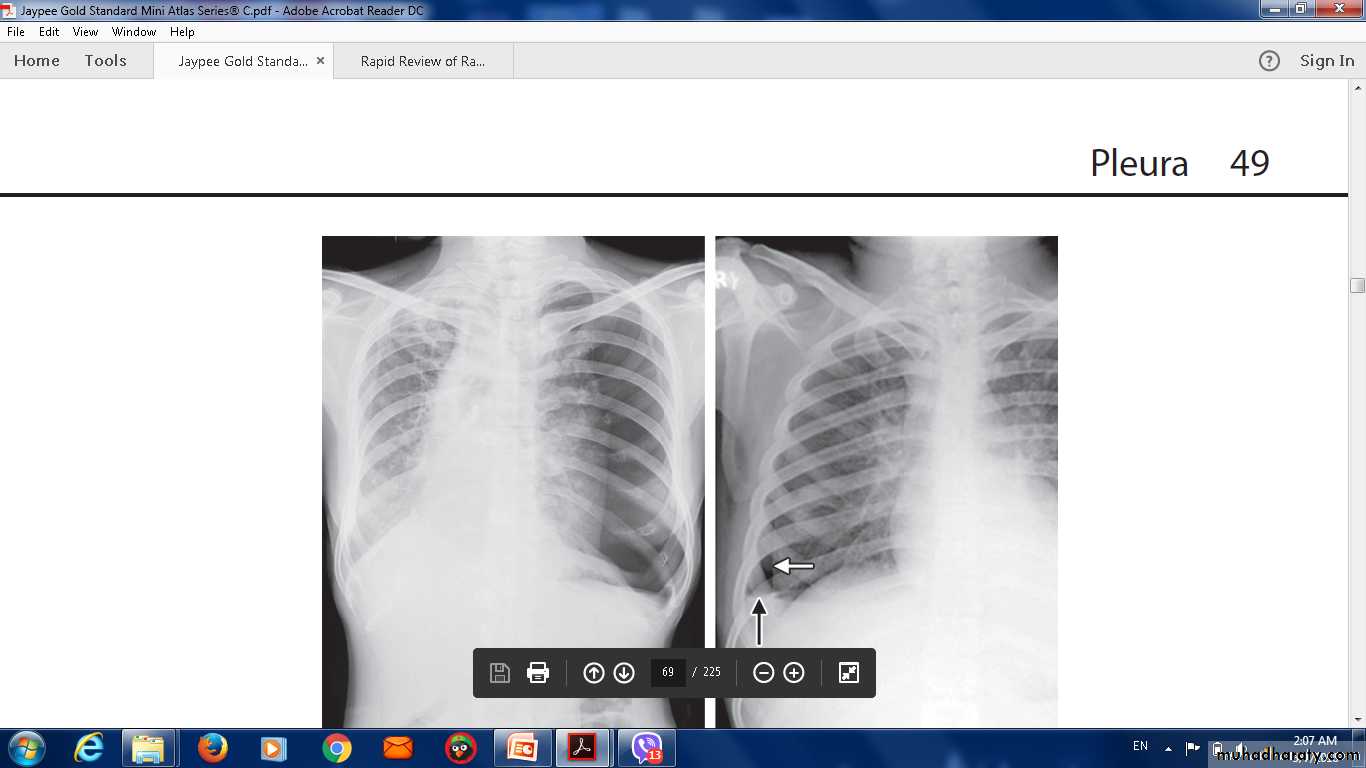

The erect PA chest film .

200 mL of fluid is required ,

ultrasound or CT smaller effusions.

Pleural fluid localised below the lower lobe ('subpulmonary effusion').

Fluid localised within an oblique fissure.

Ultrasonography is more accurate than plain chest radiography.

To distinguish pleural fluid from pleural thickening.

CT better than either plain radiography or ultrasound,.